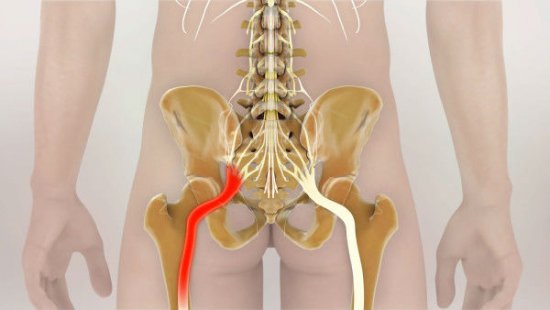

Защемление седалищного нерва

Чаще всего боли в спине появляются при проблемах с позвоночником

В большинстве случаев болевые ощущения внизу поясницы появляются в результате защемления спинномозговых нервов, что приводит к острой, или резкой боли. При этом боли сопровождаются не проходящими спазмами спинных мышц. Любые последующие попытки нормально двигаться вызывают лишь усиление боли.

Еще один источник болей в пояснице – наличие межпозвонковых грыж. При их ущемлении, сдавливании нервных корешков возникает довольно сильная, резкая боль, справиться с которой на начальных стадиях помогают стероидные и нестероидные противовоспалительные препараты.

Признаком неблагоприятного исхода является люмбалгия, которая проявляется спектром разнообразных симптомов. Боли по ходу нервного корешка могут отдавать в ягодицы и ступни. Дискомфорт появляется при наклонах (даже при наклоне головы вниз), смехе, кашле и т. д. Болевой синдром усиливается при поднятии лежа на спине прямой ноги.